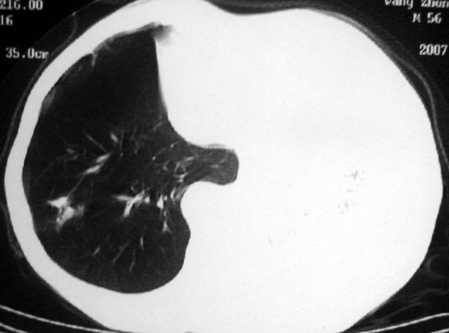

男,54岁,咳嗽,气喘半年,胸痛一月.

血性胸水

支持左肺下叶中心型肺癌(累及舌叶)伴阻塞性肺炎、膨胀不全、胸腔积液、心包少量积液。

考虑左肺下叶中央型肺癌伴阻塞性肺炎及肺不张,纵隔受累可能,胸膜转移。